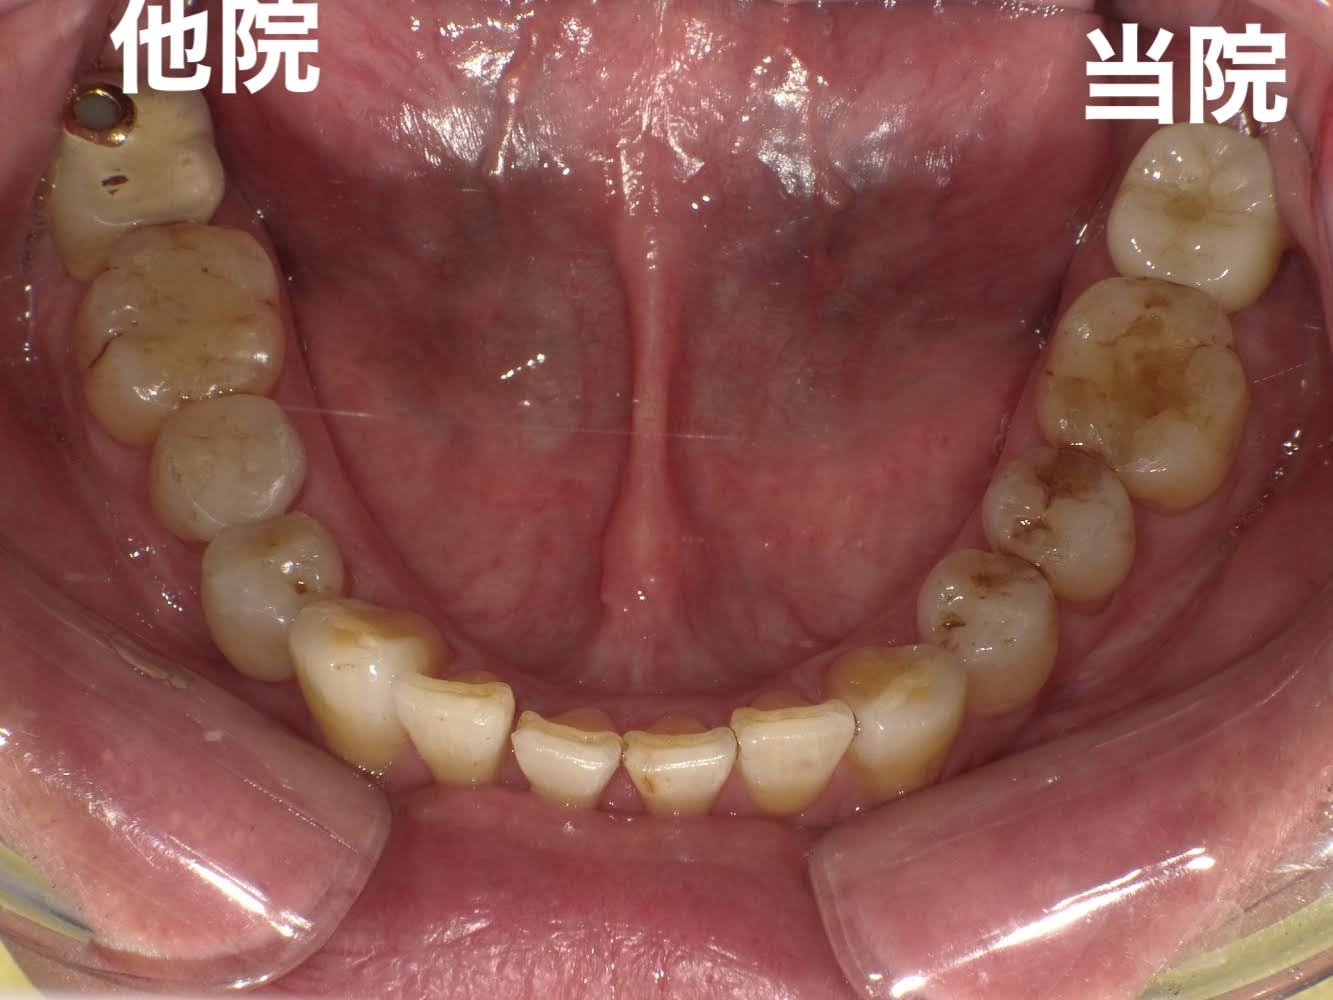

右の奥歯を過去に他院でインプラントをした方が、当院で左下や上の歯のインプラントをする為に転院してくださった患者様です。

インプラントは高額な治療ですが、どこの位置にどの角度で埋入するかが、とても大事というのがわかりやすかったので、患者様に投稿することをお願いして挙げさせていただきました。

インプラントを快適に長く使って頂くには、菌と力のコントロールが大事なのですが、前のものは位置が悪く、汚れも溜まりやすいし、咬む力も変な方向にかかってしまう仕上がりになっています。

被せ物のクオリティーもその歯科医院がどこの技工所にどのブランドで頼むかで全く変わってきます。

インプラントをご検討の方、すでに行った方は参考にしてください。

担当:理事長 佐藤悠野